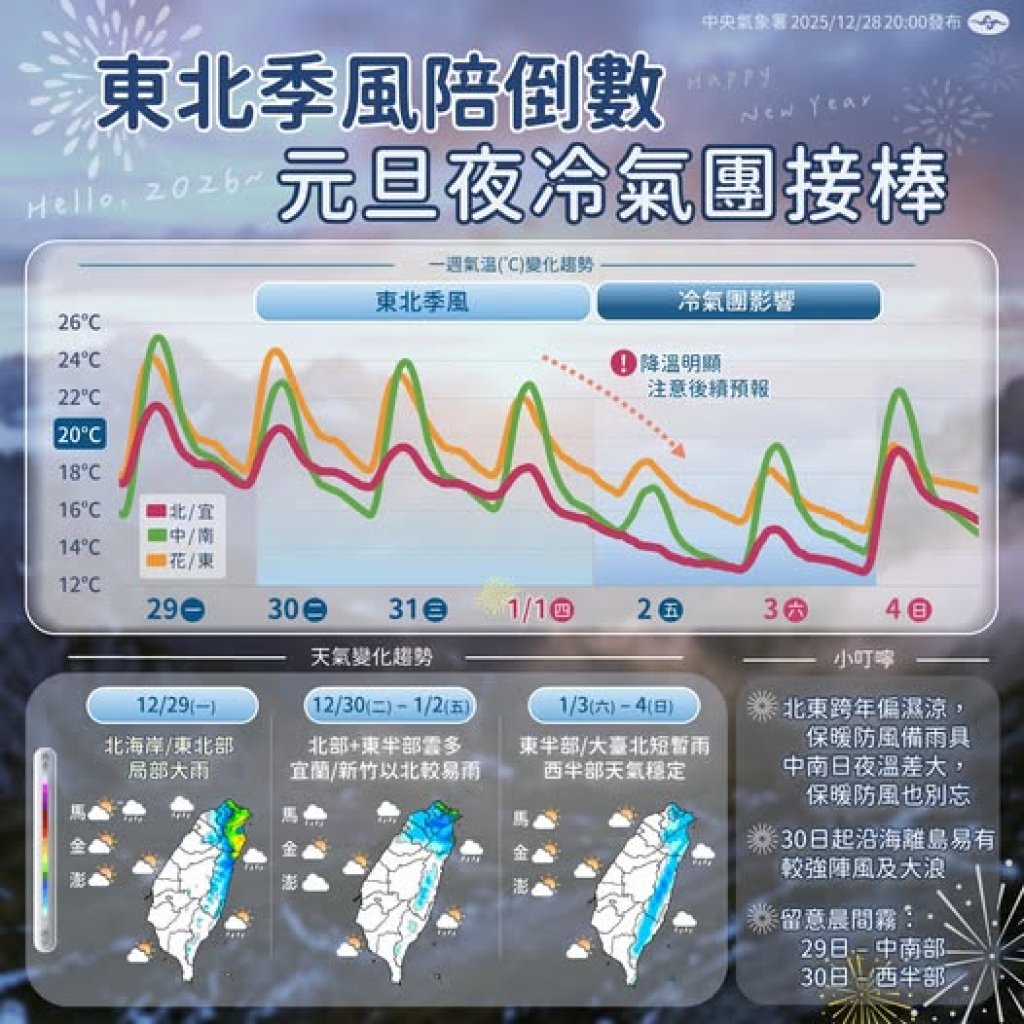

53 歲男子因持續胃痛、食慾下降而日漸消瘦,至義大癌治療醫院血液腫瘤科饒坤銘副院長門診求診。原以為只是常見的腸胃不適,經檢查後,診斷第三期胃癌,腫瘤已明顯影響胃部功能,短短時間讓他體重減輕 10 公斤。突如其來的噩耗,讓病人與家屬瞬間陷入巨大的焦慮與無助。 胃鏡(治療前)

胃鏡(治療前)